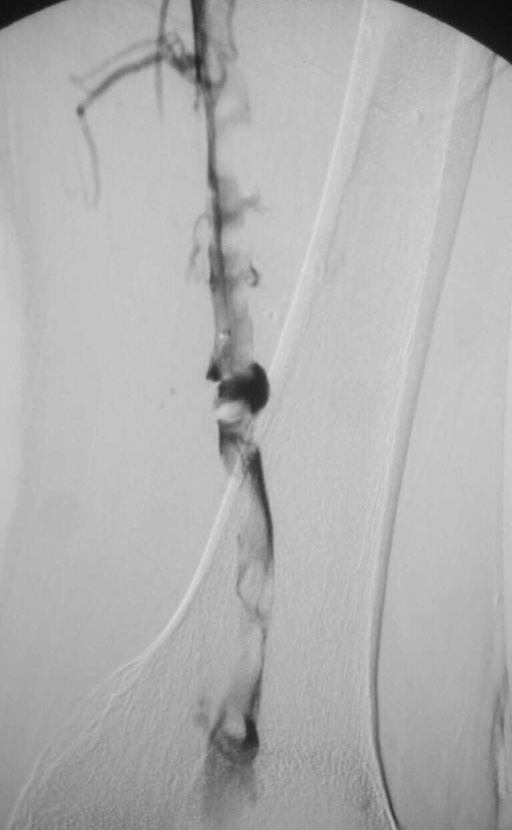

静脉造影示下肢静脉内大量血栓

下肢静脉血栓形成介入抽栓